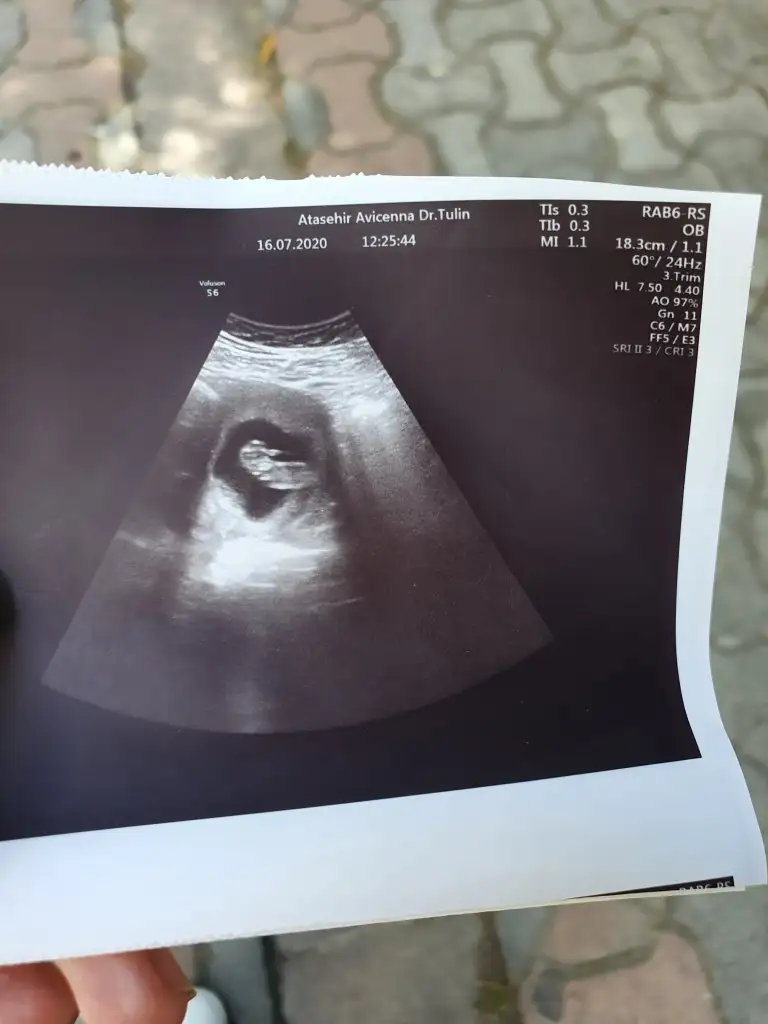

Sanki erkek gibi nubu karışık çok zor çözmek varsa başka usg paylaşın 13 hafta olursada paylaşınMerhabalar tam 12. Haftadayiz doktorum tahmin söylemiyor sizce kiz mi erkek mi bebisim cok merak ediyorumIkra meyra

Bebek hafif yan pozisyonda emin olmamakla birlikte sanki kız tekrar usg paylaşınMerhaba. Bana da tahmin de bulunur musunuz :)

12 haftalik